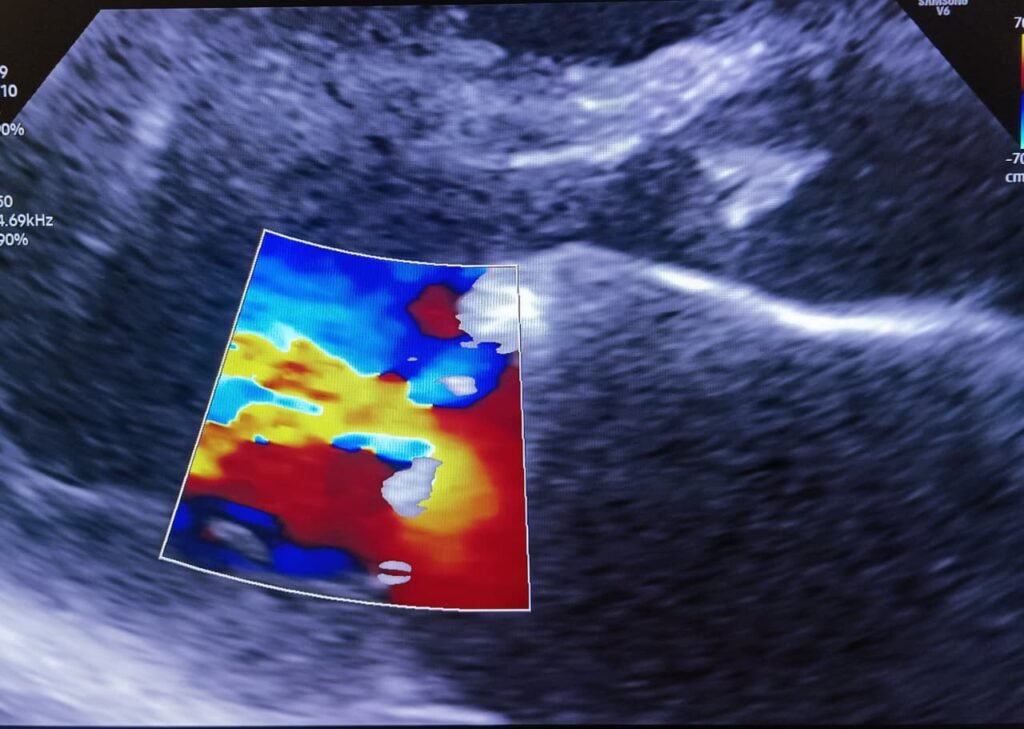

The suspicious finding prompted the senior experienced radiologist to place the probe in the subxiphoid region directed towards heart. The findings were alarming.

There was almost complete closure of one of the heart valves, namely the mitral valve, that is the connecting door between the two left sided cardiac chambers.  The valve was thickened. Very little flow of blood was observed from one into the other chamber of the heart, namely from left atrium to left ventricle.

There was evidence of back pressure into the lungs that was causing stagnation of fluid inside the thorax. And now, why the boy was having intermittent little dry cough was convincingly explained by the findings. The retention of fluid in the lungs was causing the airway symptoms.